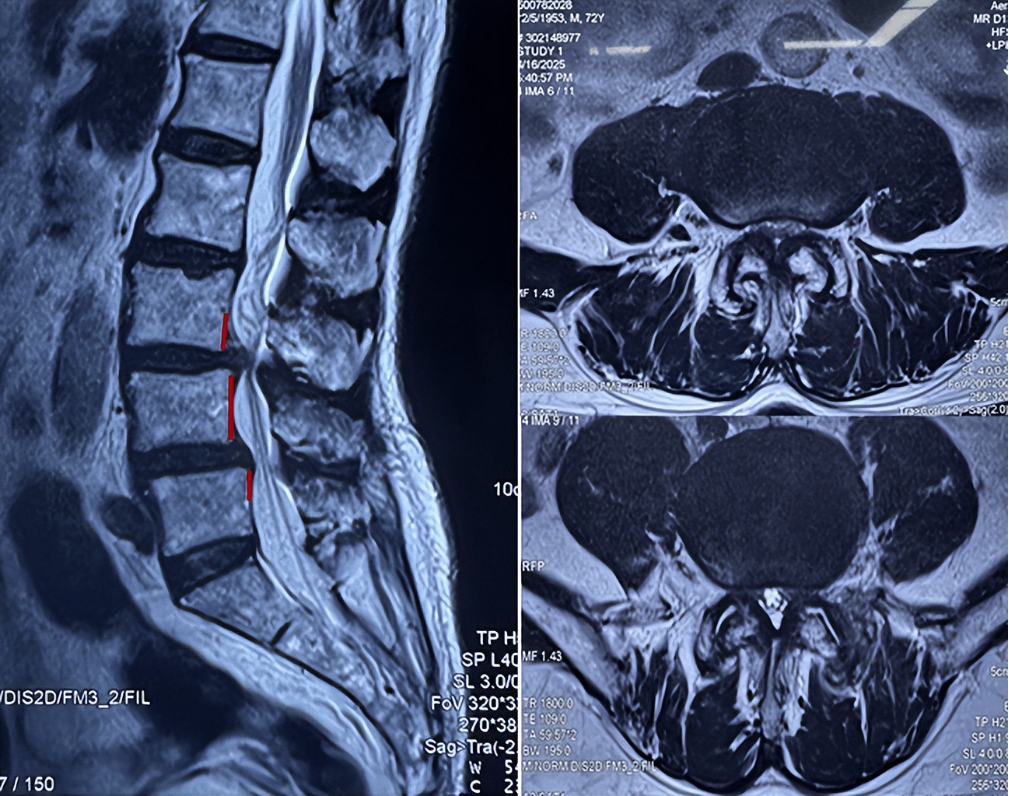

术前核磁:腰3-4、腰4-5椎体滑脱伴腰椎管狭窄

入院后,经全面检查评估,李先生病情复杂,不仅存在多节段腰椎退变问题,还伴有糖尿病、高血压等较多基础疾病,传统开放手术伤口感染发生率高,术中术后出血多导致风险增加。因此西安市红会医院脊柱病医院专家团队制定内镜微创手术治疗的方案。脊柱病医院创伤与老年脊柱病区董亮主任医师带领团队,结合患者实际情况,经过严谨讨论,最终决定采用UBE镜下微创双侧减压双间隙融合术(UBE-LIF+ULBD)。该术式可通过三个微小切口,利用双通道内镜系统,精准处理双节段病变,在有效避免大切口创伤的同时,实现充分减压与稳定融合。

手术过程中,团队凭借丰富经验与默契配合,在UBE内镜清晰视野下,依次对L3-L4、L4-L5节段进行双侧神经减压、间盘切除,并置入椎间融合器与内固定装置,复位滑脱椎体。整个手术操作精细,出血少、损伤小,成功解决了患者双节段的腰椎病变。